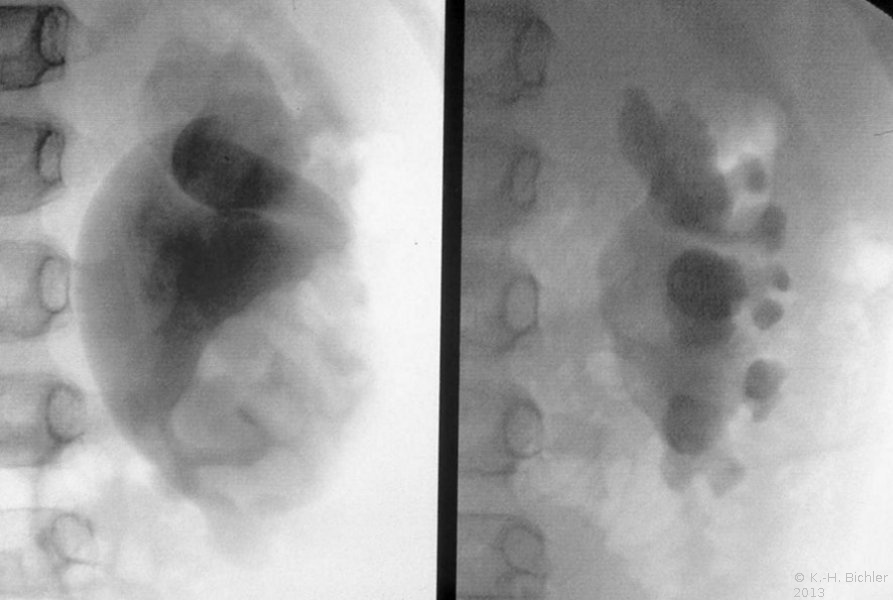

Bei dem Jugendlichen war eine Ureterabgangsstenose nach Anderson-Hynes operiert worden. Wegen postoperativem Aufstau und hochfieberhaftem Harnwegsinfekt war zunächst eine retrograde Sondierung und Einlage einer Ureterschiene erfolgt. Nach Infektbeherrschung Reoperation der Ureterabgangsstenose nach Culp (Abbildung 13).